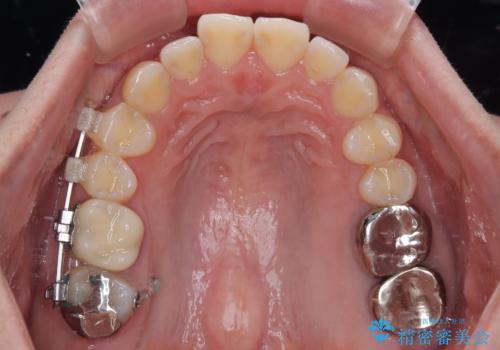

しかし、噛み合わせの相手である右上の第二大臼歯が、長期間噛み合う歯がなかった影響で**挺出(歯が下に伸びてくる状態)してしまっており、このままではインプラントを埋入して被せもの(上部構造)を入れるためのスペースが不足している状態でした。

そこで、右上の奥歯に部分的なワイヤーを装着し、さらに矯正用アンカースクリュー(TADs)を併用することで、挺出した歯を圧下(歯を元の高さに戻す動き)させ、下顎にインプラントを埋入するための十分な垂直的スペースを確保しました。

→ この装置は部分的な矯正で、前歯など見える位置にワイヤーがかかることはなく、見た目を気にすることなく、普段通りの生活を送りながら治療を進めることができました。